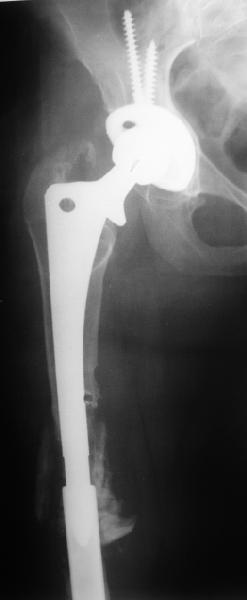

Female, rheumatoid, THA in 2003, car accident in 2006, failed plating. Nailing in Oct 2007. The nail is solid with hollow proximal part where the stem is docked. Last images are in 1 year after

nailing.

The lady walks fine and doesn't bleed ;-)

The femur responded by failure to Mennen plating (DePuy Bridge plate). So i would add that the ability to unite is realized in mechanically and biologically sound conditions.